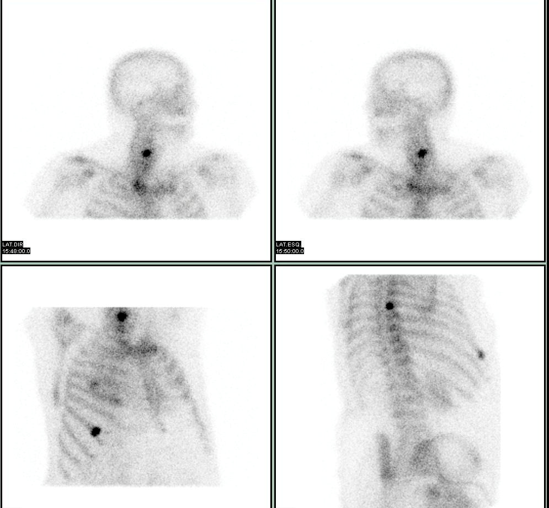

Cintilografia

4 lesões ósseas